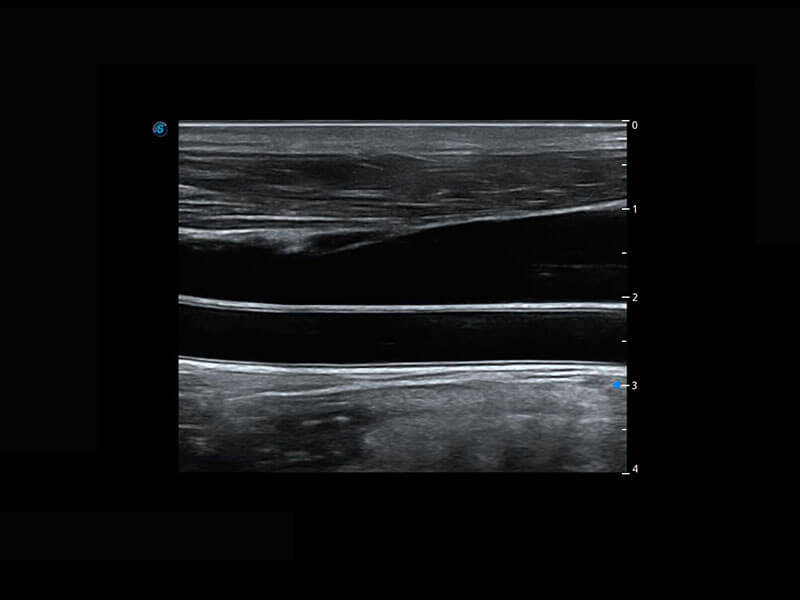

P60搭载宽频带线阵探头、宽景成像、弹性成像技术,为您提供乳腺应用方案。P60支持高频相控阵探头、线阵探头、腹部高频探头、腹部微凸探头等,丰富的探头群搭载敏感的彩色血流成像,适用于新生儿多种脏器检测要求,满足新生儿筛查需求。

乳腺导管癌

乳腺癌显微血流

新生儿脊髓圆锥